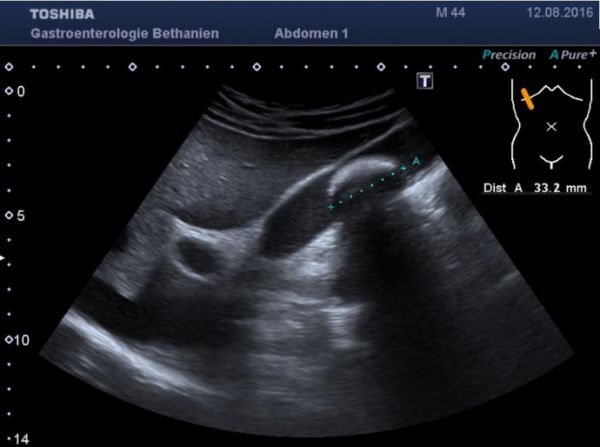

Der Bauchultraschall ermöglicht die risikofreie Darstellung der Leber, der Gallenblase, des Darmes und weiterer Organe und Strukturen im Bauch. Dabei wird ein Gel auf die Ultraschallsonde gegeben und mit der Sonde über den Bauch gefahren, um die verschiedenen Organe auf Abnormitäten zu untersuchen. Die Bilder können direkt am Monitor mitverfolgt werden.

Ursachen sind Leberzirrhose, Entzündung oder Tumor. Aszites muss häufig punktiert werden. Mittels Ultraschall wird die Stelle für die Flüssigkeitsentnahme festgelegt, auf der Bauchhaut markiert und eine Kanüle zur Untersuchung oder Entlastung eingeführt. Die Untersuchung wird in der Regel ambulant durchgeführt.